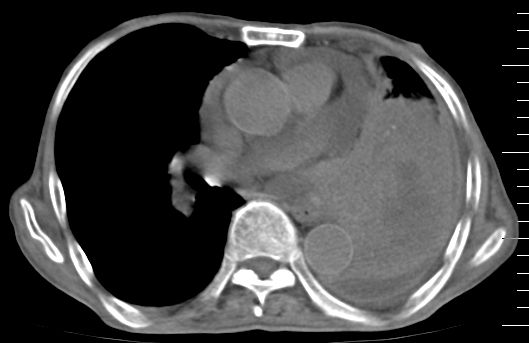

标题: CT10141:男、84岁,咳嗽、咯血1年。 [打印本页]

标题: CT10141:男、84岁,咳嗽、咯血1年。

支持左侧中央型肺癌伴下叶肺不张\\纵隔淋巴结转移.左侧包裹性胸腔积液\\心包积液.左侧少量胸腔积液..慢性支气管炎伴部分间质纤维化.

支持:左侧中央型肺癌伴下叶肺不张\\纵隔淋巴结转移.左侧包裹性胸腔积液\\心包积液.左侧少量胸腔积液..慢性支气管炎伴部分间质纤维化.另:支气管分支根部明显阻塞 狭窄,内膜凸凹不平,提示内膜增生物。

咯血病史较长,左肺下叶实变,体积未明显缩小,隐约可见血管影及坏死阴影,双肺门及纵隔淋巴结增大,心包增厚积液,纵隔右移位,单侧胸腔积液,首先考虑:大叶型肺泡癌伴纵隔心包转移。